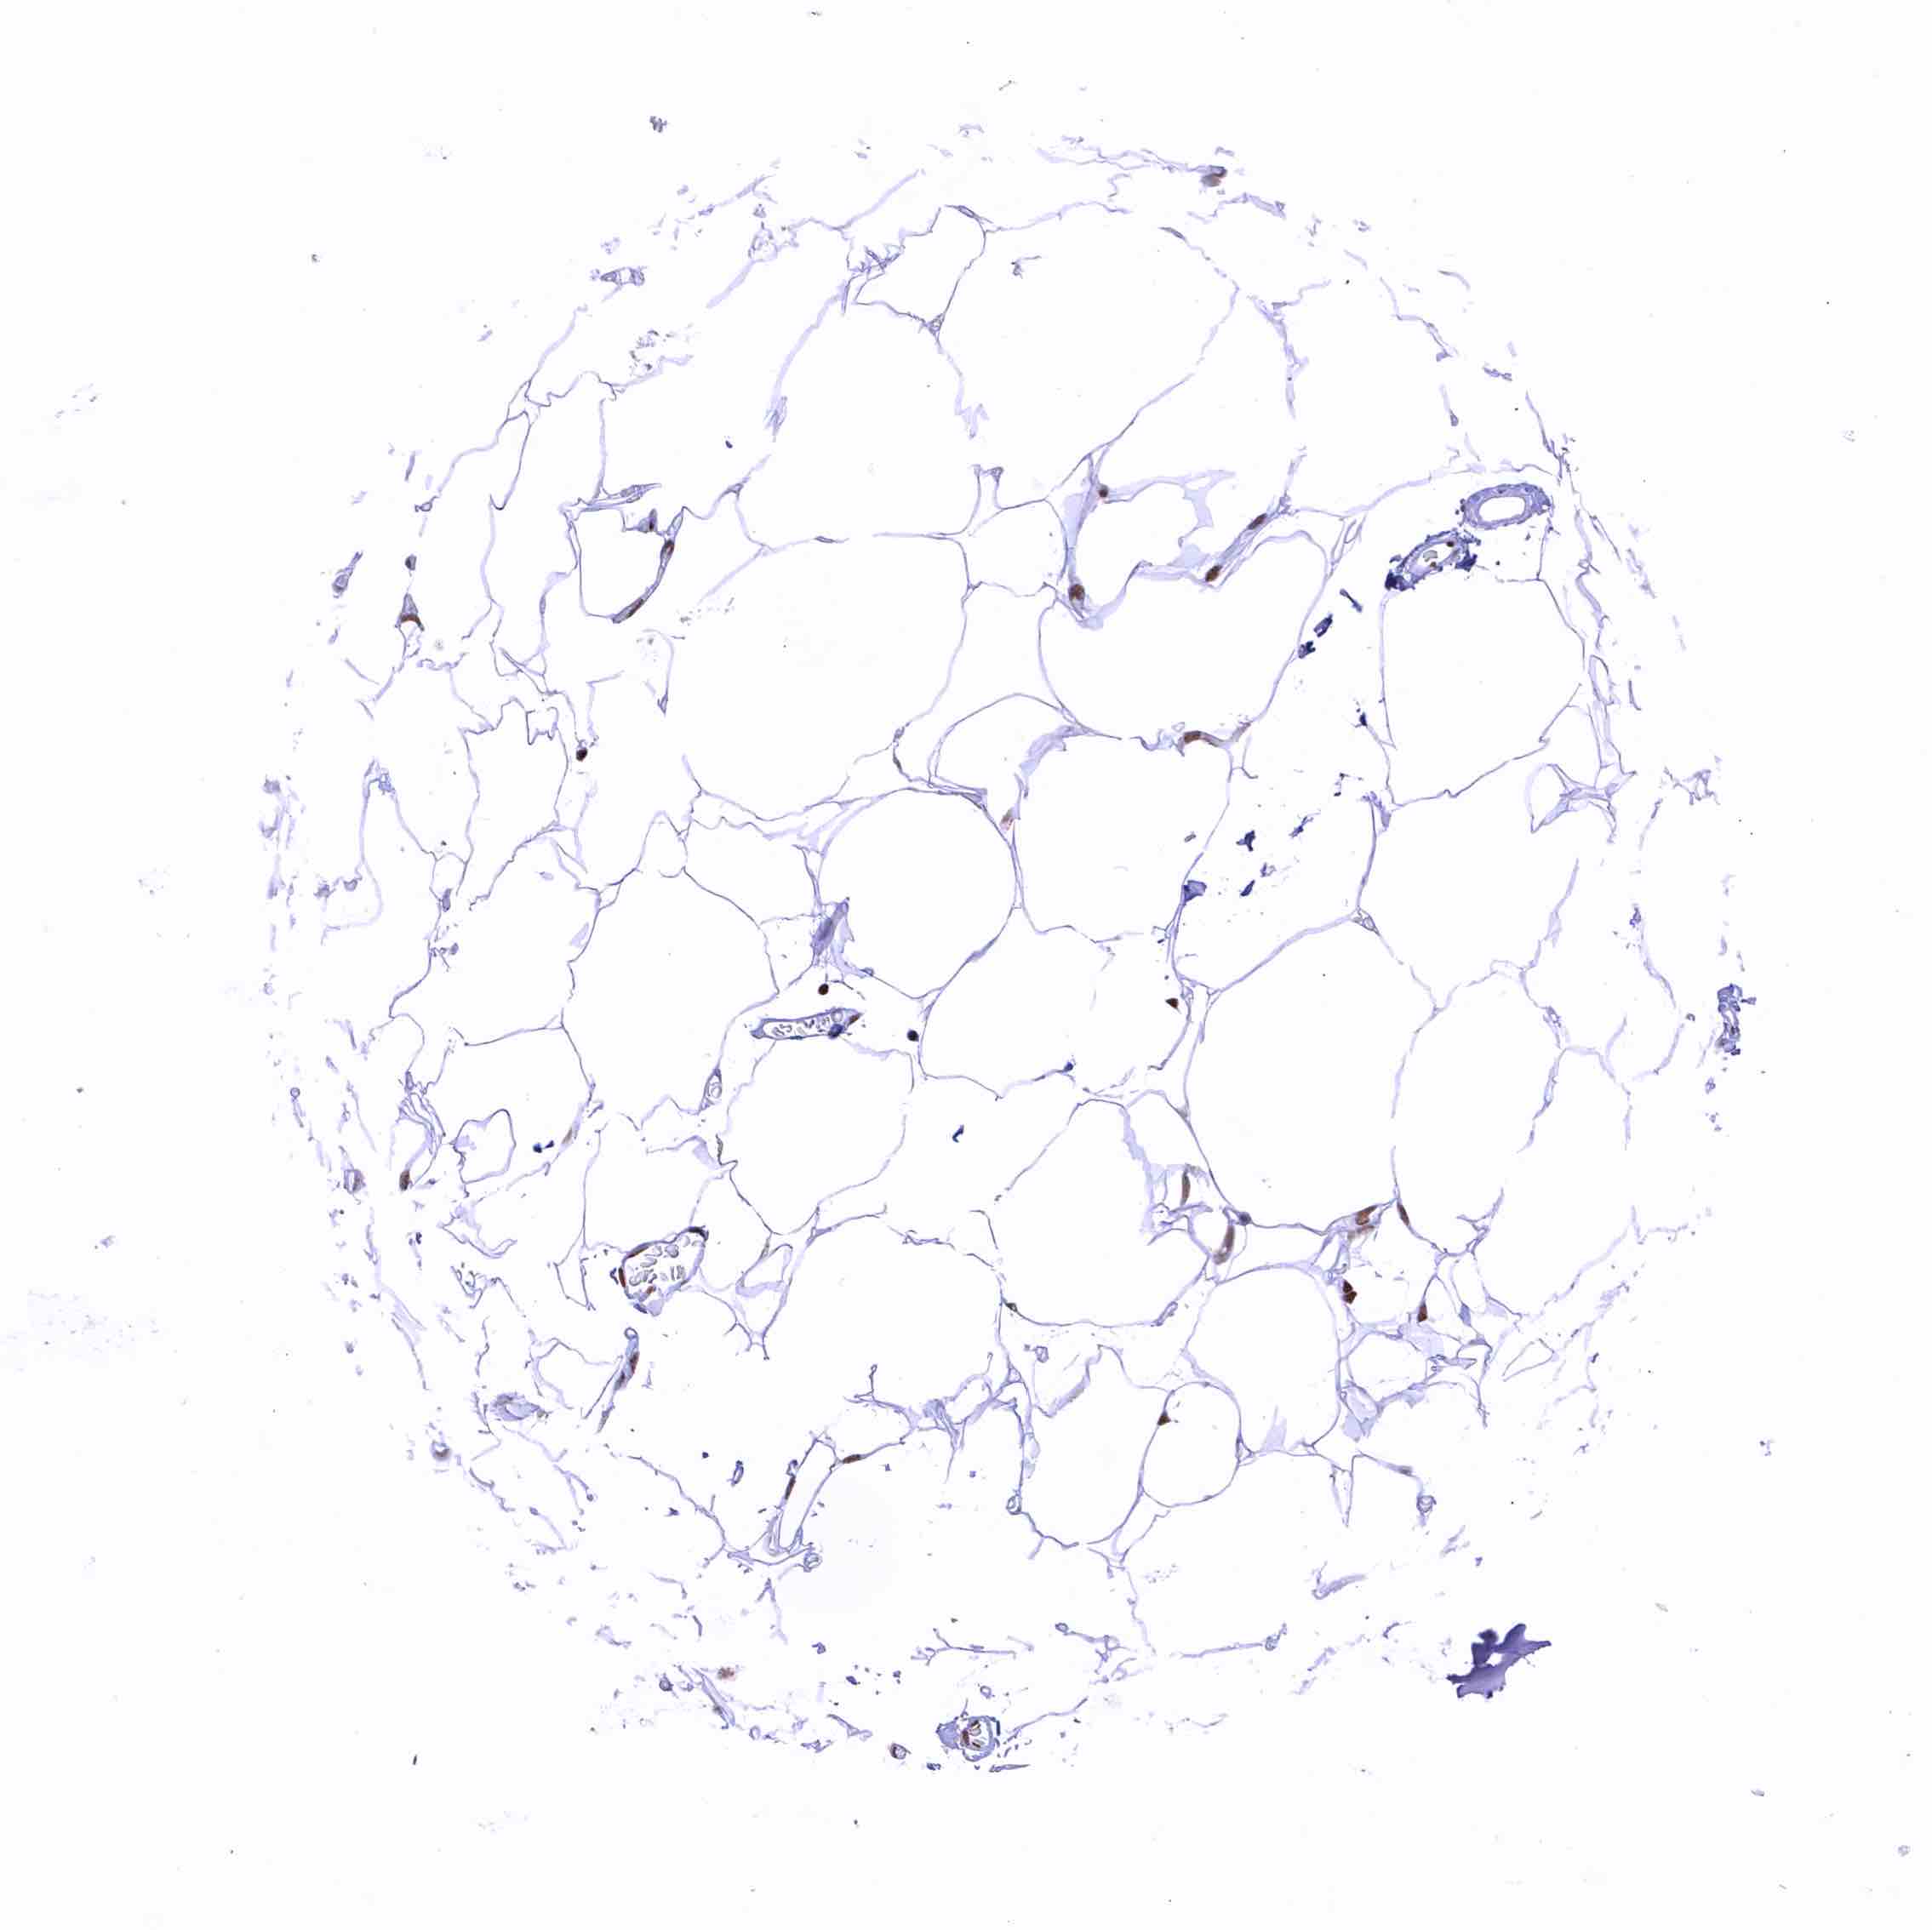

Fat